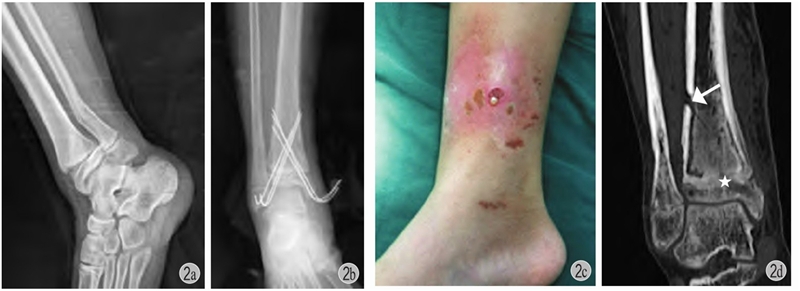

图1 患儿 女12岁

a:左胫骨远端三平面骨折;b、c:切开复位,空心钉+克氏针固定,空心钉平行骺板且位于骨骺内,辅以斜行克氏针穿越骺板固定